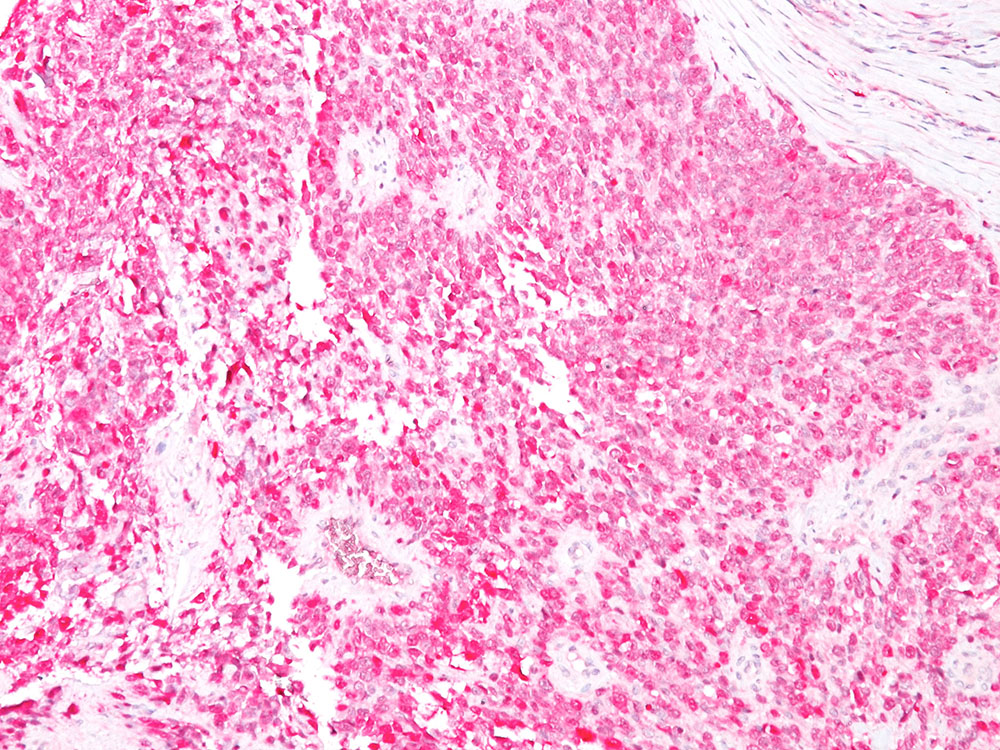

Formalin-fixed, paraffin-embedded human melanoma stained with S100 Ab (4C4.9).